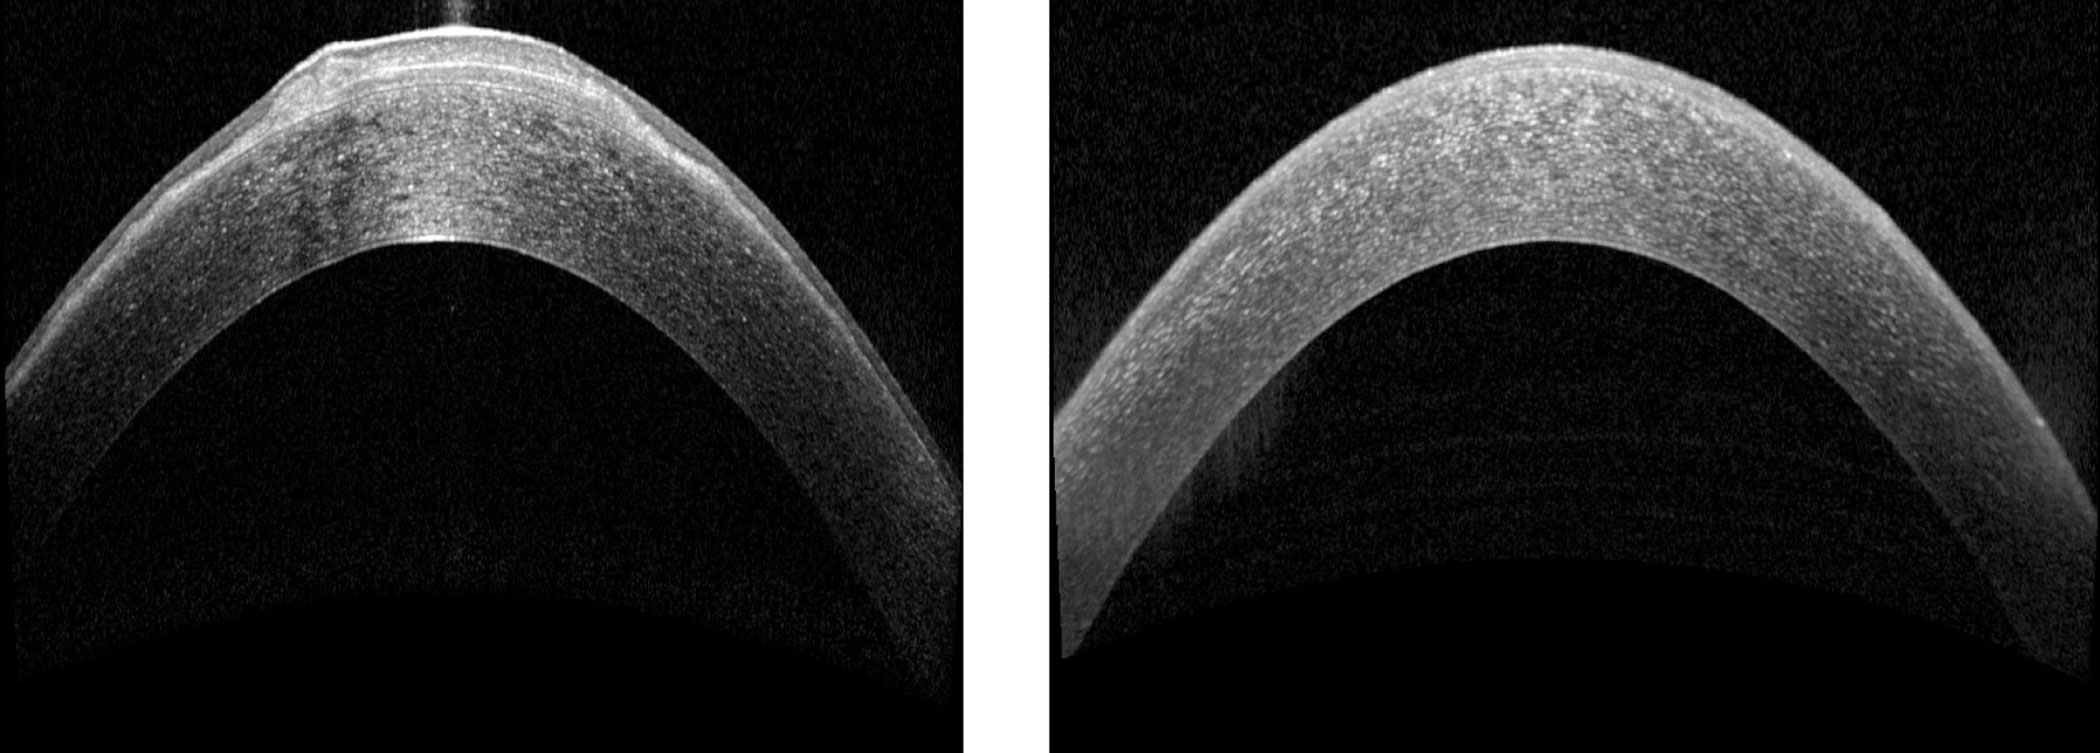

Figure 2: Anterior segment OCT of the right eye preoperatively and postoperatively presented from left to right respectively.

Baseline slit-lamp photography and AS-OCT is presented in Figure 1 and Figure 2 respectively. Corneal pentacam looking at the anterior corneal axial curvature before and after the operation, as well as a difference map, are presented in Figure 3.

The patient underwent alcohol delamination of the right corneal epithelium. The histology later revealed focally disrupted Bowman’s layer and variable epithelial thickness with sub-epithelial scarring - features of EBMD. A bandage contact lens was inserted postoperatively and preservative-free topical steroids and antibiotics were commenced. Three days postoperatively the visual acuities were 6/5 OU. Postoperative corneal topography revealed corneal flattening of the right eye and complete resolution of refractive error. Symptomatically, the blurring of vision resolved and the patient was pain free.